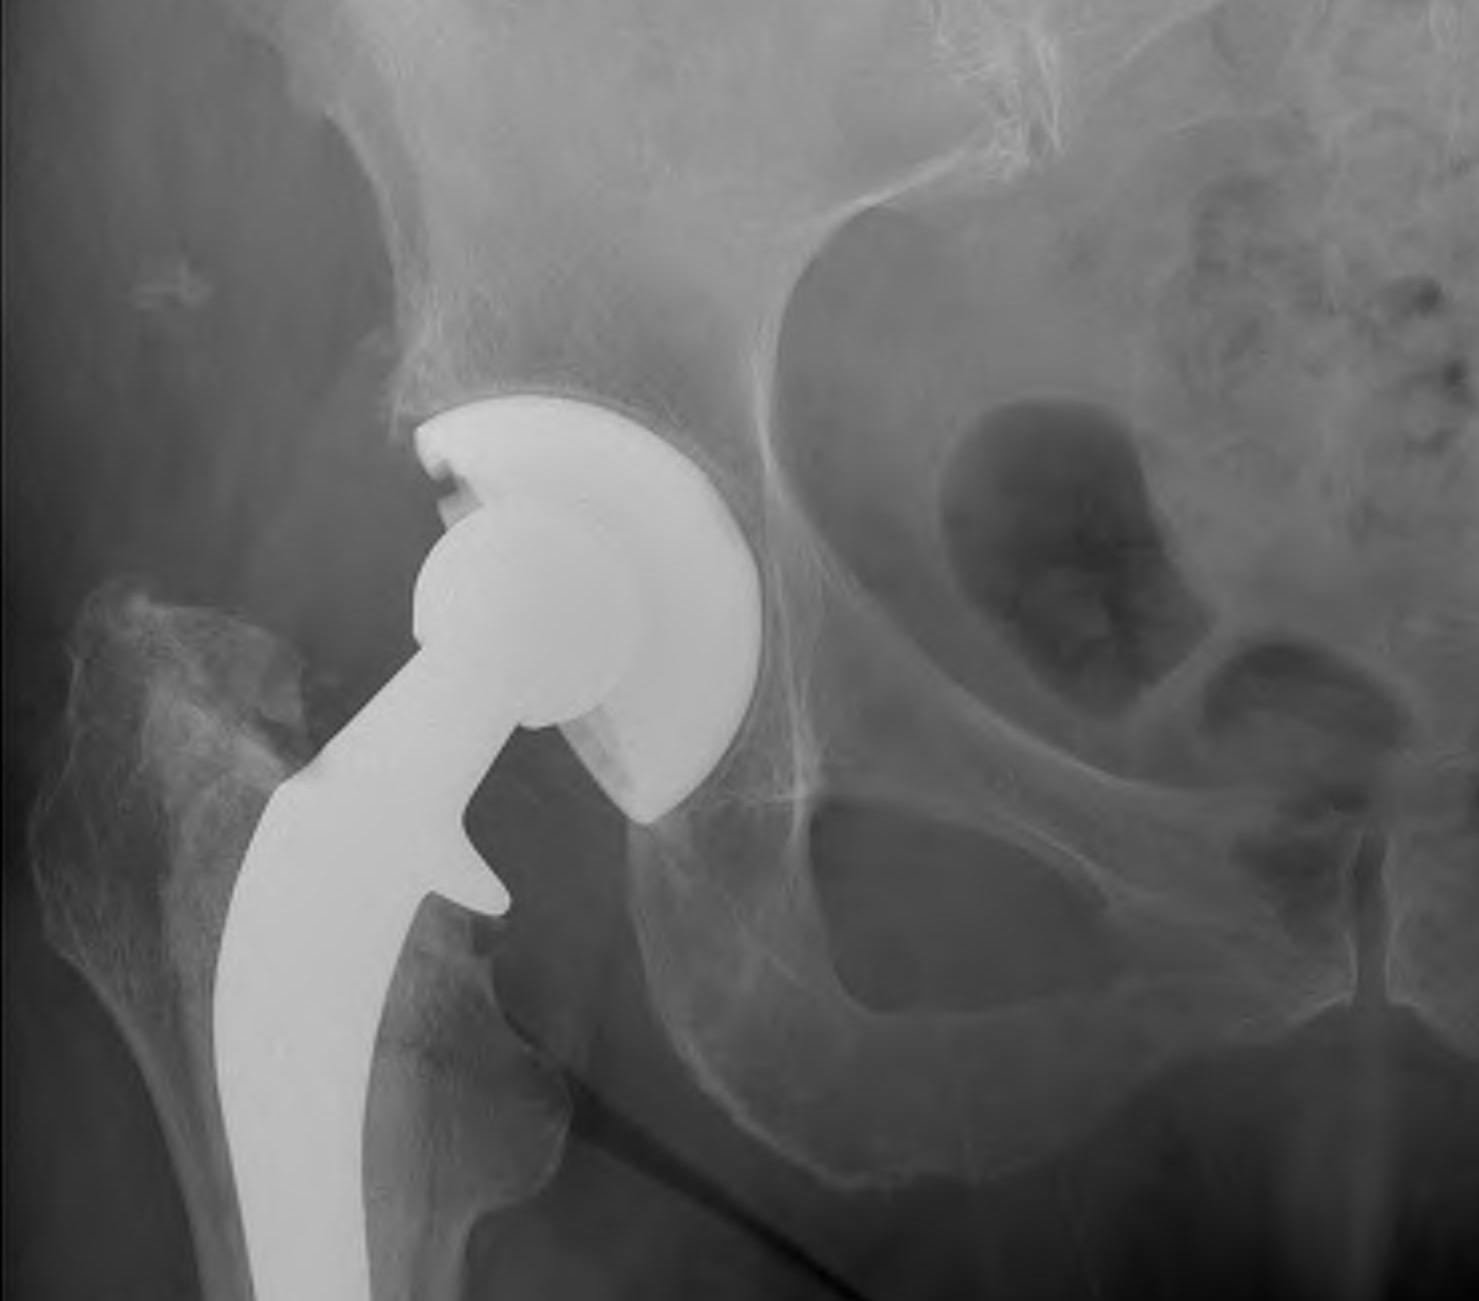

Cemented Femur

Signs of cemented femoral component loosening

O'Neil & Harris JBJS Am'84

1.  Possible

Bone-cement lucency < 50% total

- may be due to poor cementing technique

- loosening if progressive

Cemented Femur Possible Loose

2.  Probable

Cement-implant radiolucent line >2mm wide

- progressive

Cemented Femur Probably Loose

3.  Definite

1.  Cement fracture

2.  Femoral stem fracture

3.  New lucency cement - implant interface

4.  Stem migration

THR Probably LooseTHR Exeter Stem Fracture

A.  Subsidence

- 1-2 mm normal in first year

- > 5 mm abnormal

- measure from tip GT to head neck junction

B.  Medial midstem pivot

- pivots about midstem

- proximal medial, distal lateral

- poor cement superomedial or inferolateral

C.  Calcar pivot / bending cantilever

- distal fix strong, but proximally loose

- breakdown of proximal cement

- bone destruction